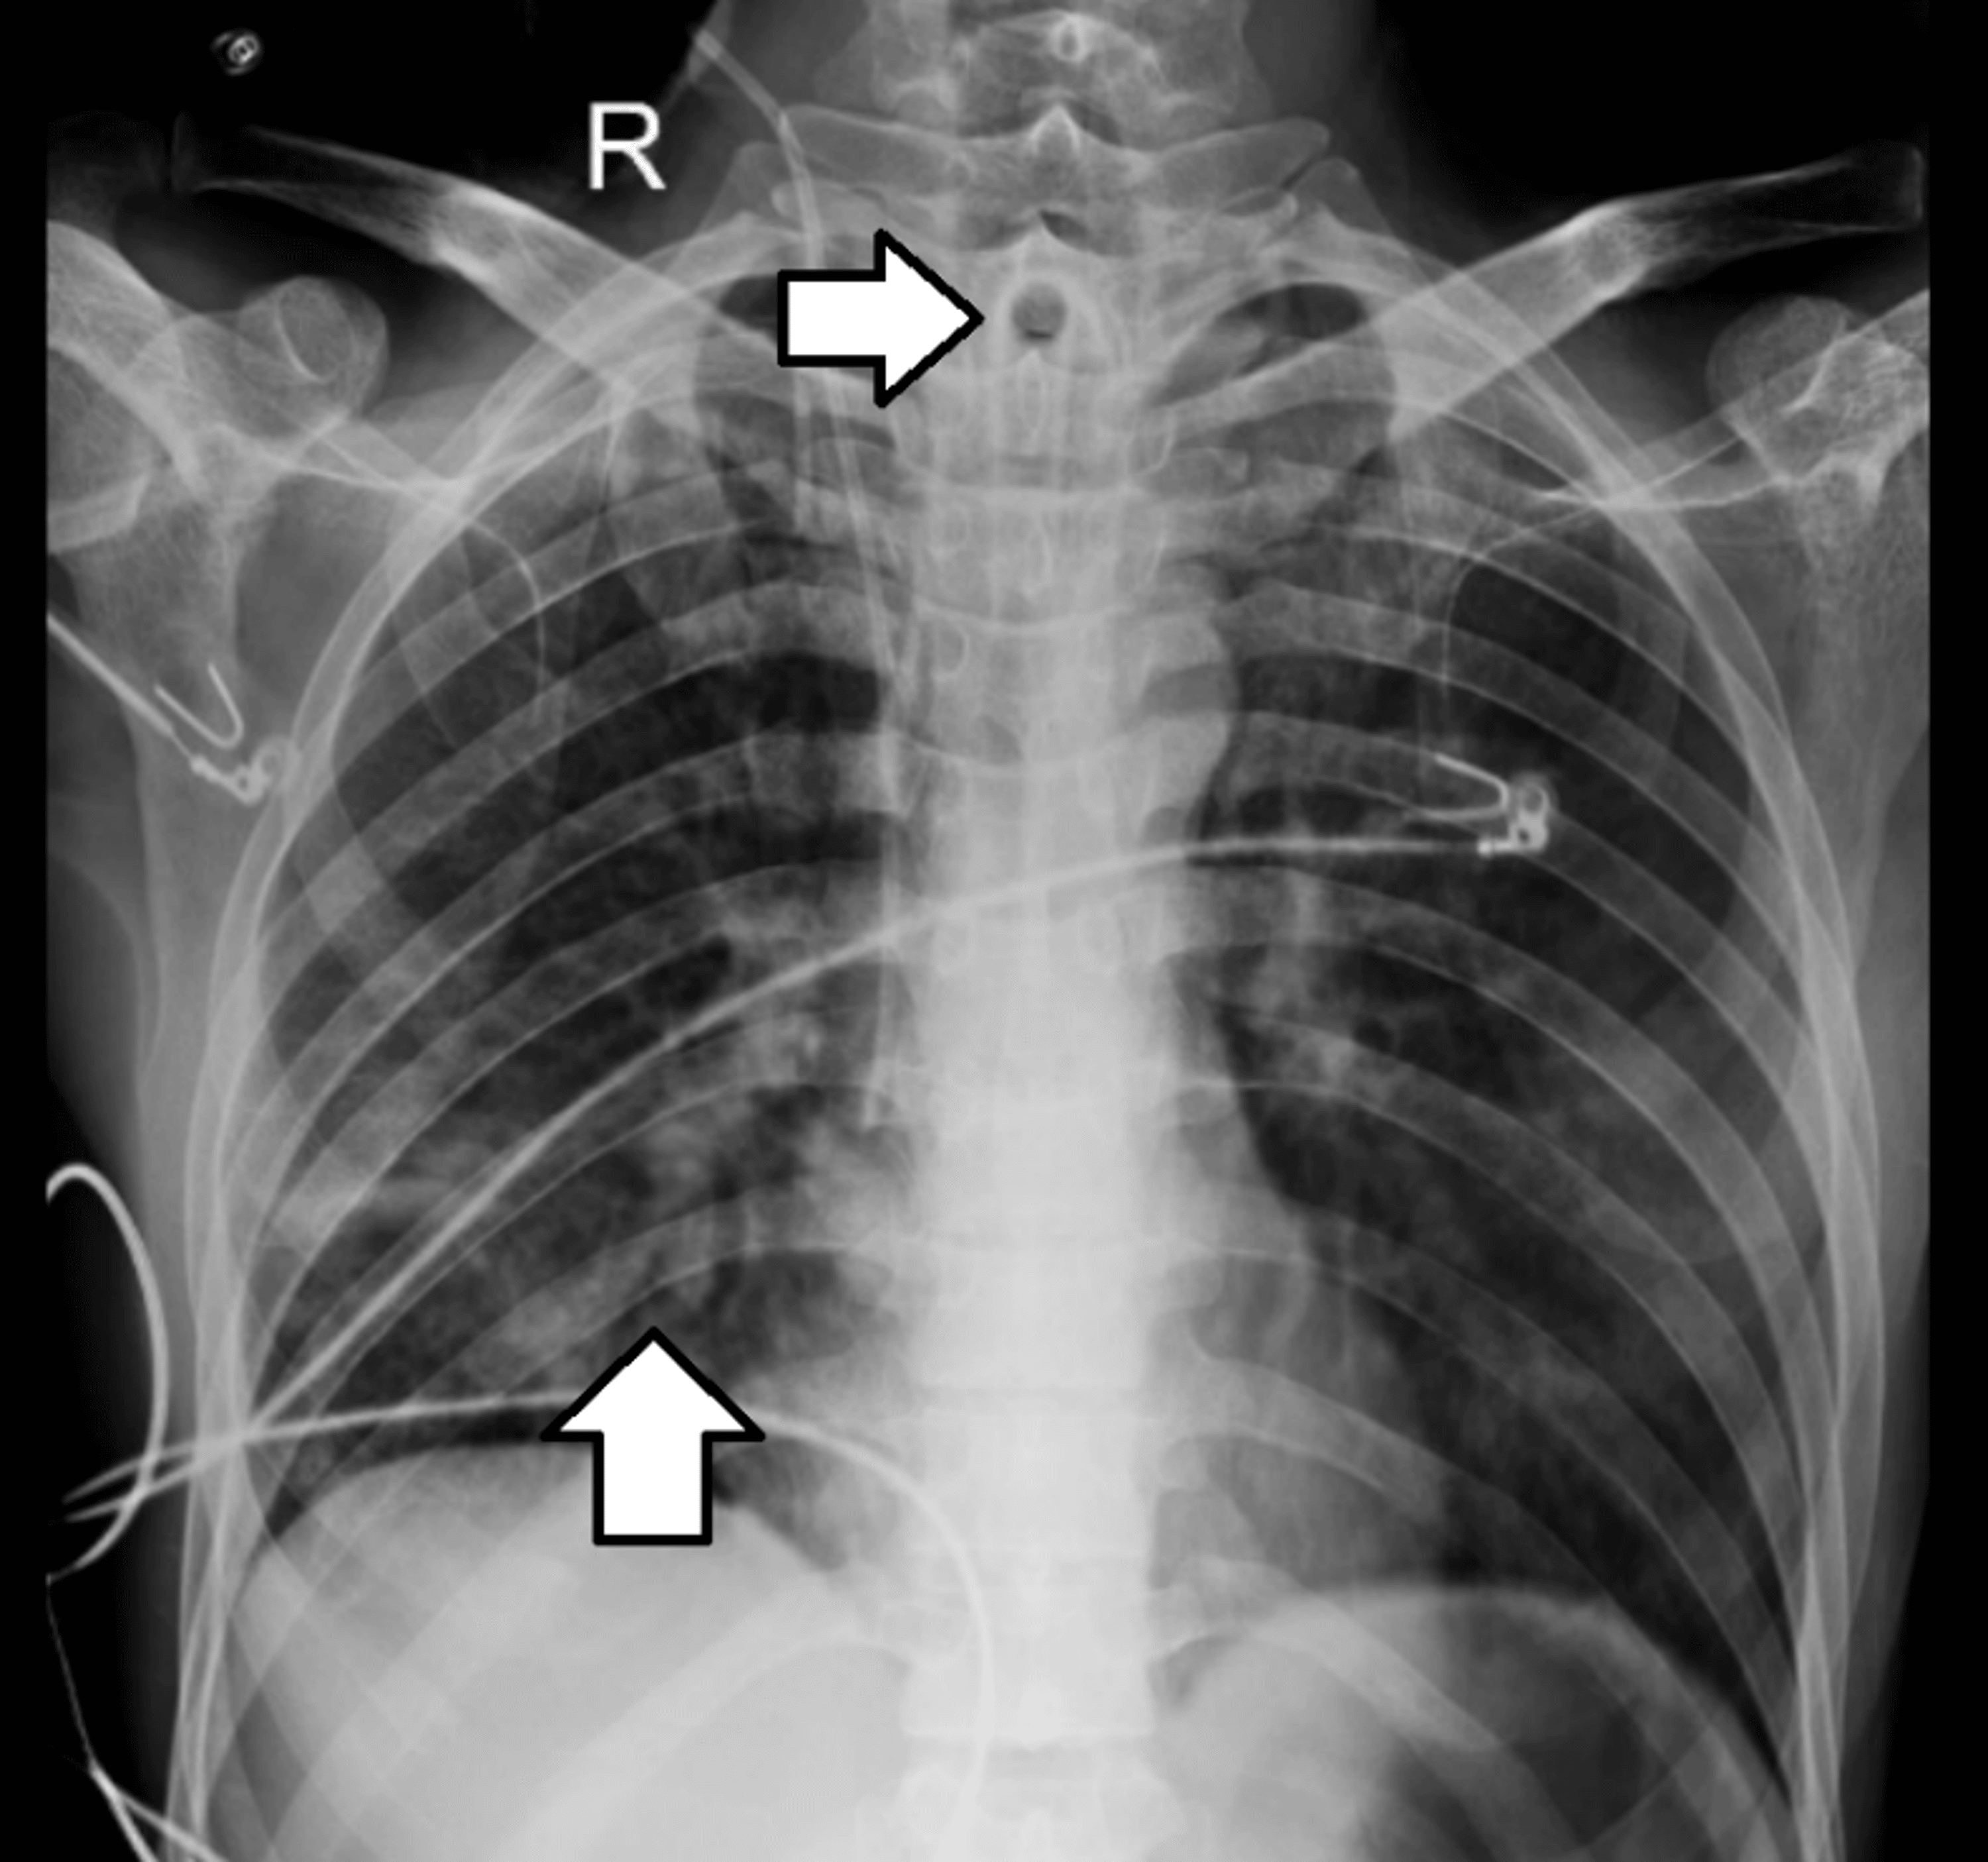

From first10em.com

Respiratory distress in the patient with a tracheostomy First10EM Tracheostomy Tube Occlusion Keep inner cannula of dual tracheostomy tube in situ at all times. Resting respiratory rate of <18. — it has been demonstrated that patients who successfully pass a tracheostomy tube occlusion protocol can. — obstruction of a tracheostomy tube is a common cause of respiratory compromise in adults and pediatric patients, which can lead to a life. . Tracheostomy Tube Occlusion.